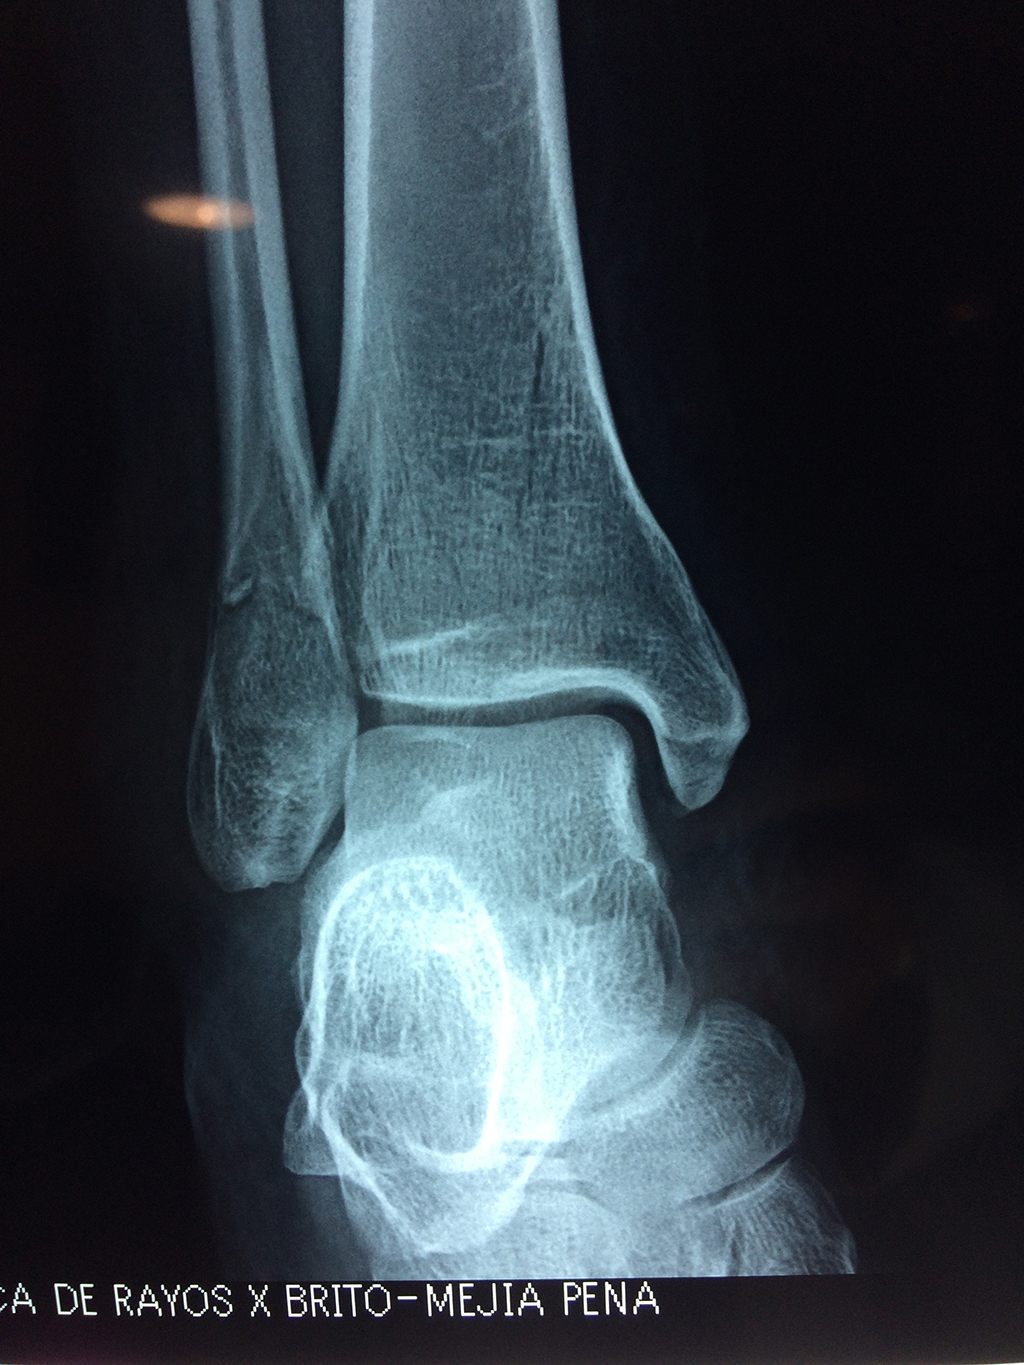

Una fractura de tobillo es la rotura de uno o más de los huesos del tobillo. Estas fracturas pueden ser:

- Los extremos de los huesos están desalineados entre sí (desplazados).

- La fractura se extiende hasta la articulación del tobillo (fractura intra-articular).